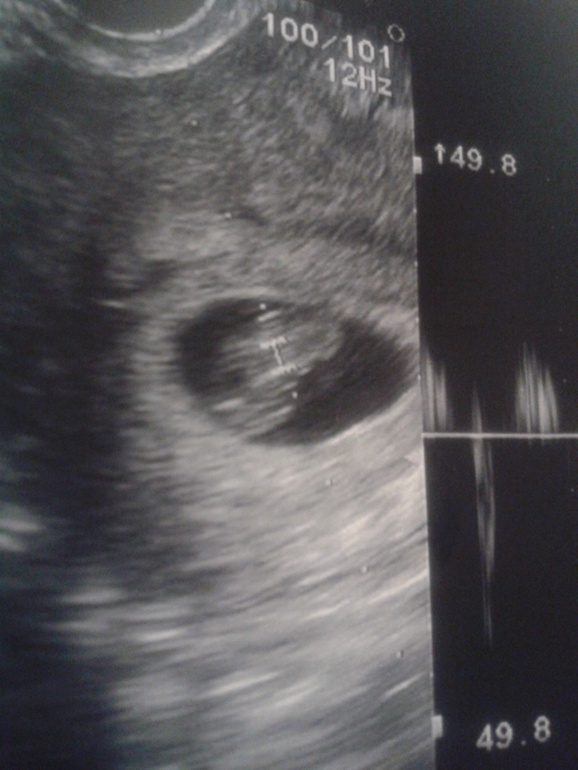

Пришла с УЗИ, 7,6

Вторая беременность7 недель и 6 дней)

Одно плодное яйцо 28мм, 1 эмбрион 14мм) желт.меш. 5мм)

ЧСС 169 ударов в минуту))

в ЛЯ ЖТ 30 на 17мм

голова внизу,спинкой к верху))